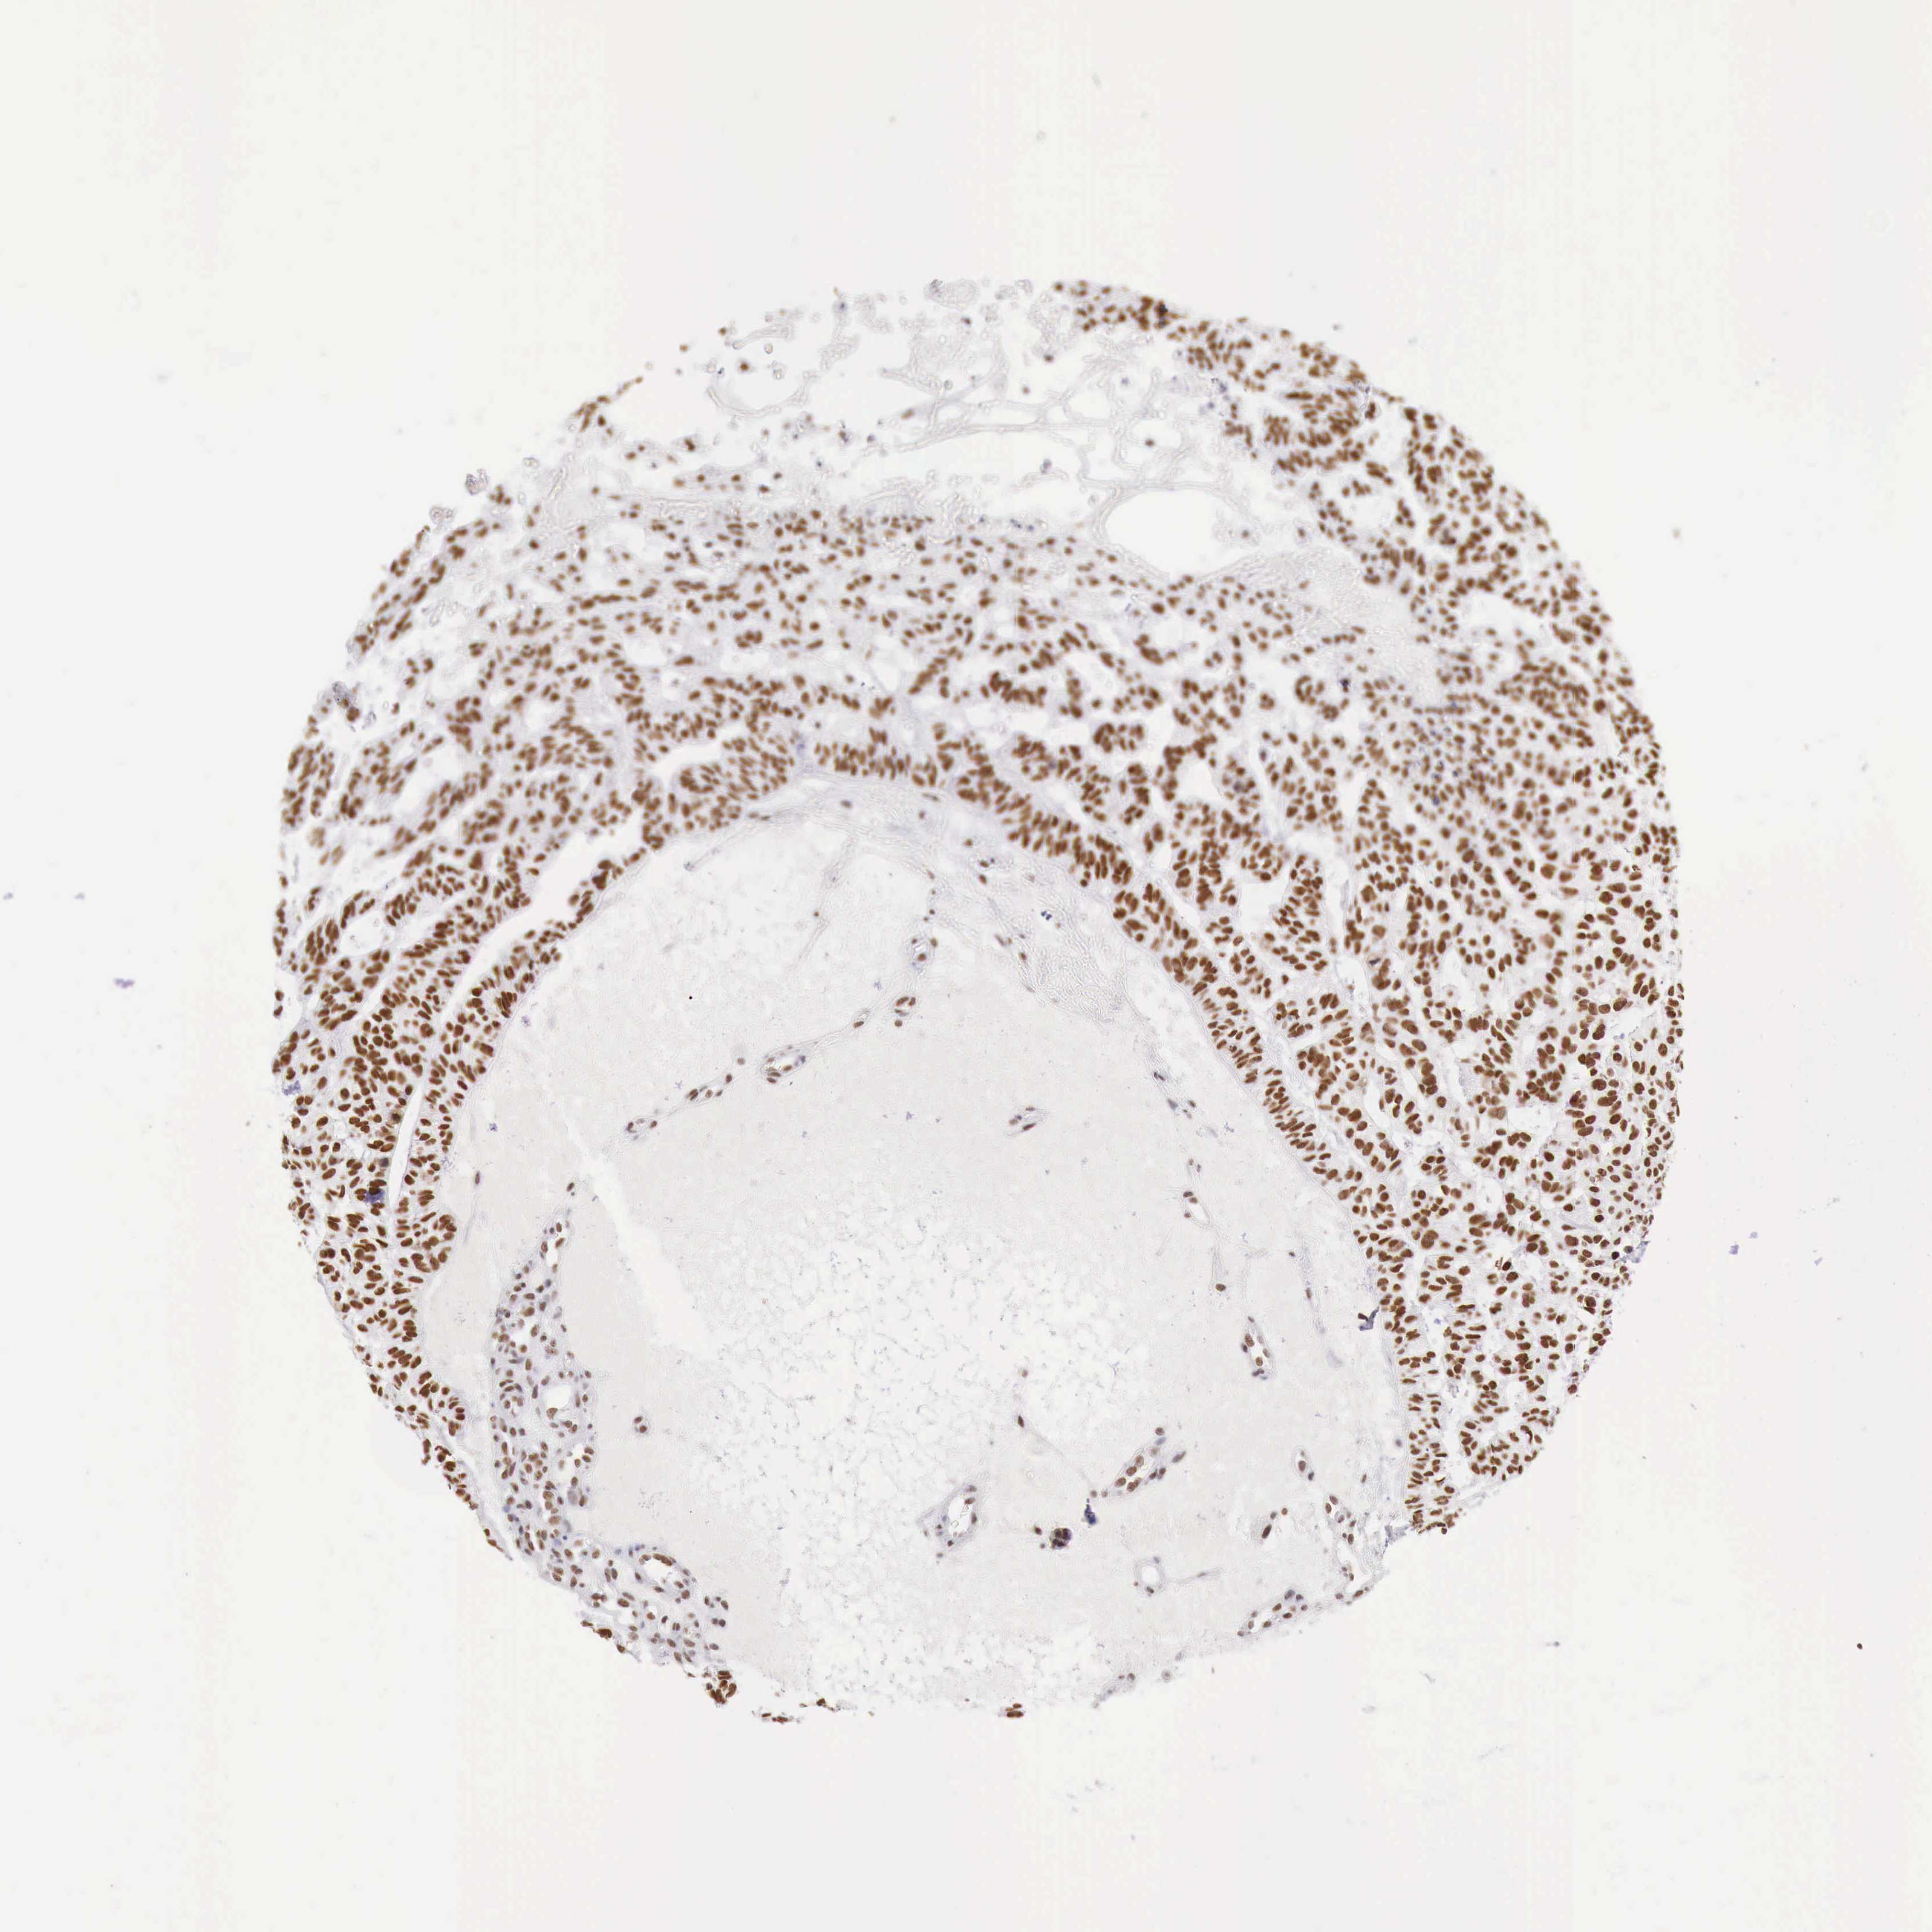

SKIN CANCER - Protein expressioni

A mouse-over function shows sample information and annotation data. Click on an image to view it in a full screen mode. Samples can be filtered based on level of antibody staining by selecting one or several of the following categories: high, medium, low and not detected. The assay and annotation is described here.

Antibody staining in the annotated cell types in the current human tissue is reported as not detected, low, medium, or high, based on conventional immunohistochemistry profiling in selected tissues. This score is based on the combination of the staining intensity and fraction of stained cells.

Each image is clickable and will lead to virtual microscopy that enables deeper exploration of all samples and also displays staining intensity scores, fraction scores and subcellular localization as well as patient and tissue information for each sample.

Antibody HPA000538

Staining

Medium

Intensity

Weak

Quantity

75%-25%

Location

Nuclear

Basal cell carcinoma